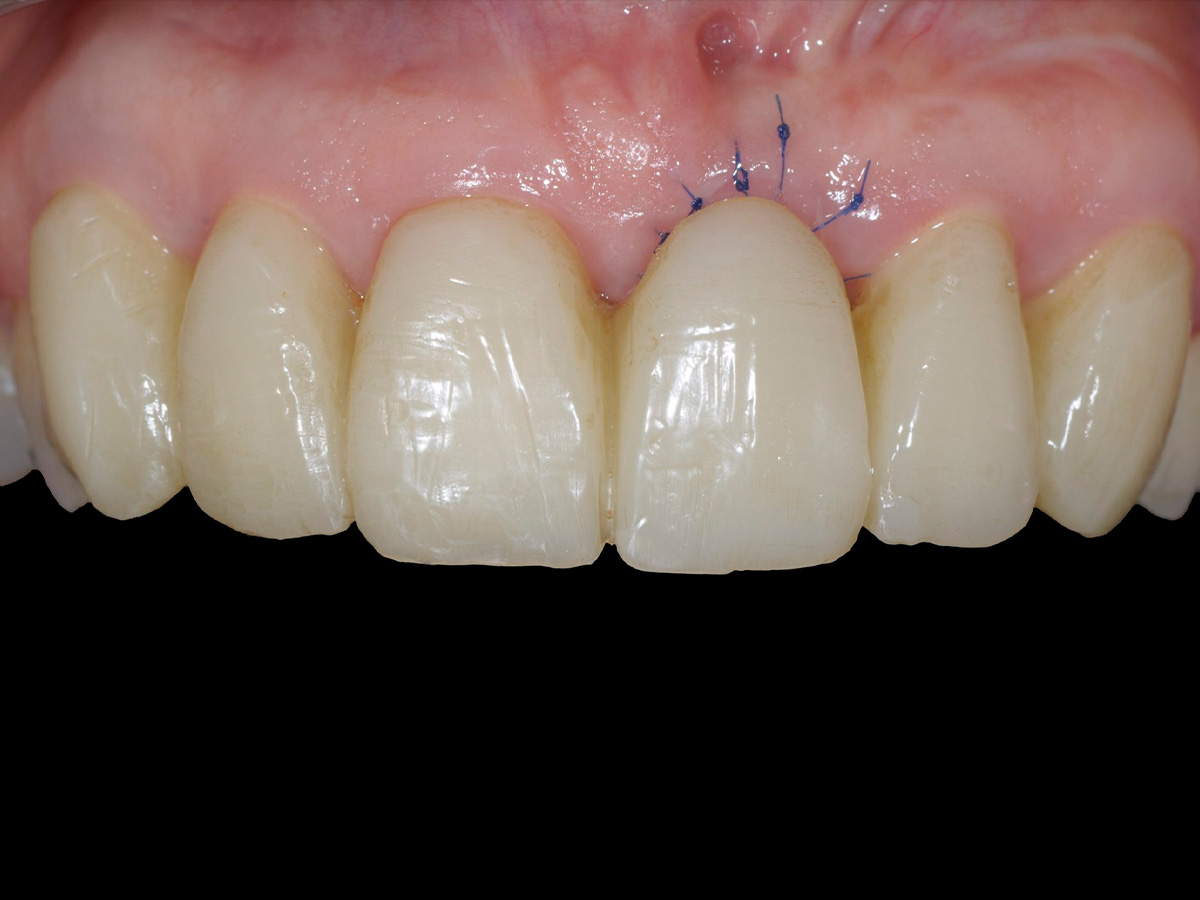

Abbildung 10

Wundverschluss.